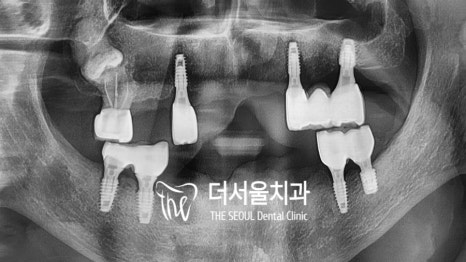

육안 관찰을 통해 확인해 본 결과

상황이 정말 좋지 않았습니다.

다수의 치아가 상실된 것은 물론이며

틀니를 지지하기 위해 남아있는

3개의 잔존치 마저 고정력을 잃었는데요.

심한 치조골 소실로 인해 동요가 나타났으며

치주 질환이 진행되어 잇몸의 상태도

좋지 않음을 알 수 있었습니다.

네비게이션 분석을 통해 식립 위치,

픽스처의 종류 등을 결정한 뒤 수술까지 마쳤는데요.

다행히 아무런 문제 없이 잘 마칠 수 있었습니다.